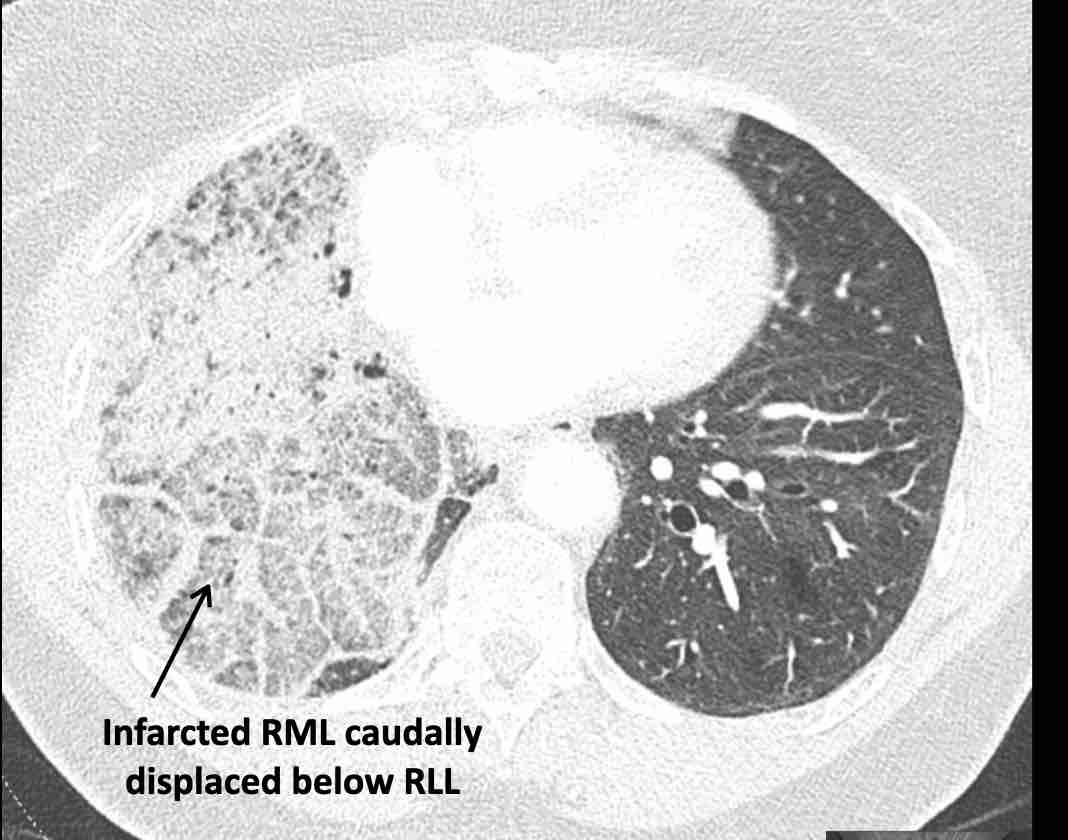

Các hình ảnh này của một bệnh nhân nữ 65 tuổi sau khi đã cắt thùy trên phổi phải trước đó.

Trước tiên, hãy cuộn qua các hình ảnh.

Hình ảnh

Theo dõi lần lượt các phế quản giúp xác định mỏm cắt thùy trên phổi phải (RUL), phế quản thùy giữa bị tắc nghẽn và các phế quản thùy dưới còn thông.

Điều này xác định mô phổi bị di lệch xuống dưới chính là thùy giữa phổi phải (RML), thấy rõ nhất trên mặt phẳng đứng dọc.

Thùy giữa phổi phải bị phù nề và không còn được tưới máu.

Ngoài ra còn thấy hình ảnh ứ máu và xẹp phổi ở các phân thùy đáy của thùy dưới phổi phải (RLL), hiện nằm phía trên thùy giữa phổi phải đã bị nhồi máu.